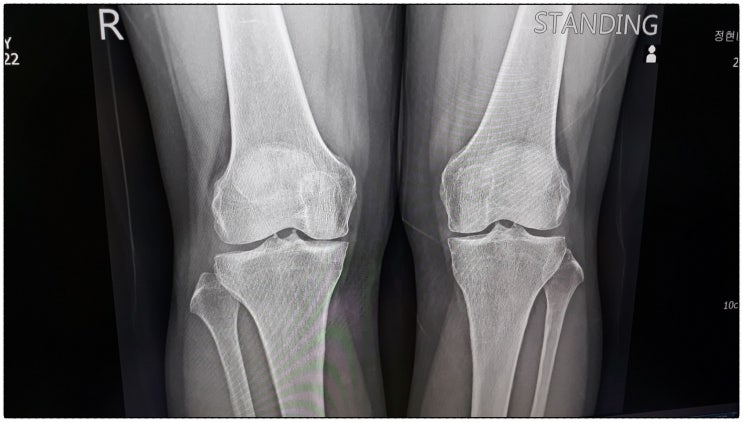

무릅 연골 관절 영양제(뮤코다당 단백 콘드로이친 프로업 1200)

이제 꽃다지도 무릅 건강이 점점 나빠지는 나이가 된듯합니다. 그동안 우리 효손들 돌보느라 정신없이 지내...

무릎관절 영양제 챙기며 통증 걱정은 훨훨 날려보네요!

관절영양제는 연세 지긋한 분들이 챙겨드리는건지 알았는데요. 저희 남편 나이가 이제 30대 중반인데 관절...

무릎통증 러닝 달리기만하다가 먹어본 관절영양제 추천

오늘은 무릎통증 러닝 달리기만하다가 먹어본 관절영양제 추천해보려고해요! 요즘 다들 러닝 많이 하시죠? ...